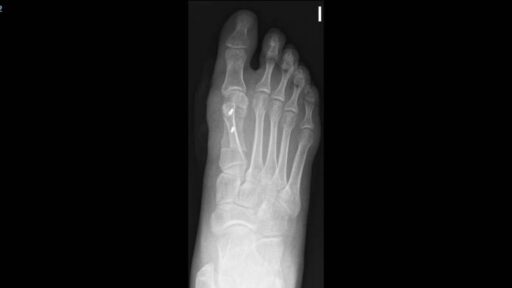

La cirugía de hallux valgus o juanete no debería realizarse si no hay dolor o dificultades para caminar. En este artículo explicamos por qué es mejor evitar intervenciones innecesarias y qué alternativas existen cuando el problema no afecta la funcionalidad del pie.

Cirugía ortopédica Opciones de tratamiento para Hallux valgus – Juanete

Opciones de tratamiento para Hallux valgus – Juanete